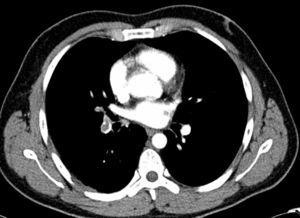

De esta forma se identificaron 18 pacientes con un diagnóstico radiológico de TEP (fig. 1) que no había sido sospechado en el examen clínico, lo que supone un 0,33% de los informes revisados. Los 18 estudios fueron evaluados por dos observadores que confirmaron el diagnóstico de TEP en todos los pacientes y valoraron su extensión.

Fig. 1. Corte de 8 mm de grosor de una tomografía computarizada torácica con contraste intravenoso a la altura de ambas arterias lobares inferiores: defecto de repleción en arterias del lóbulo inferior derecho y lóbulo medio.